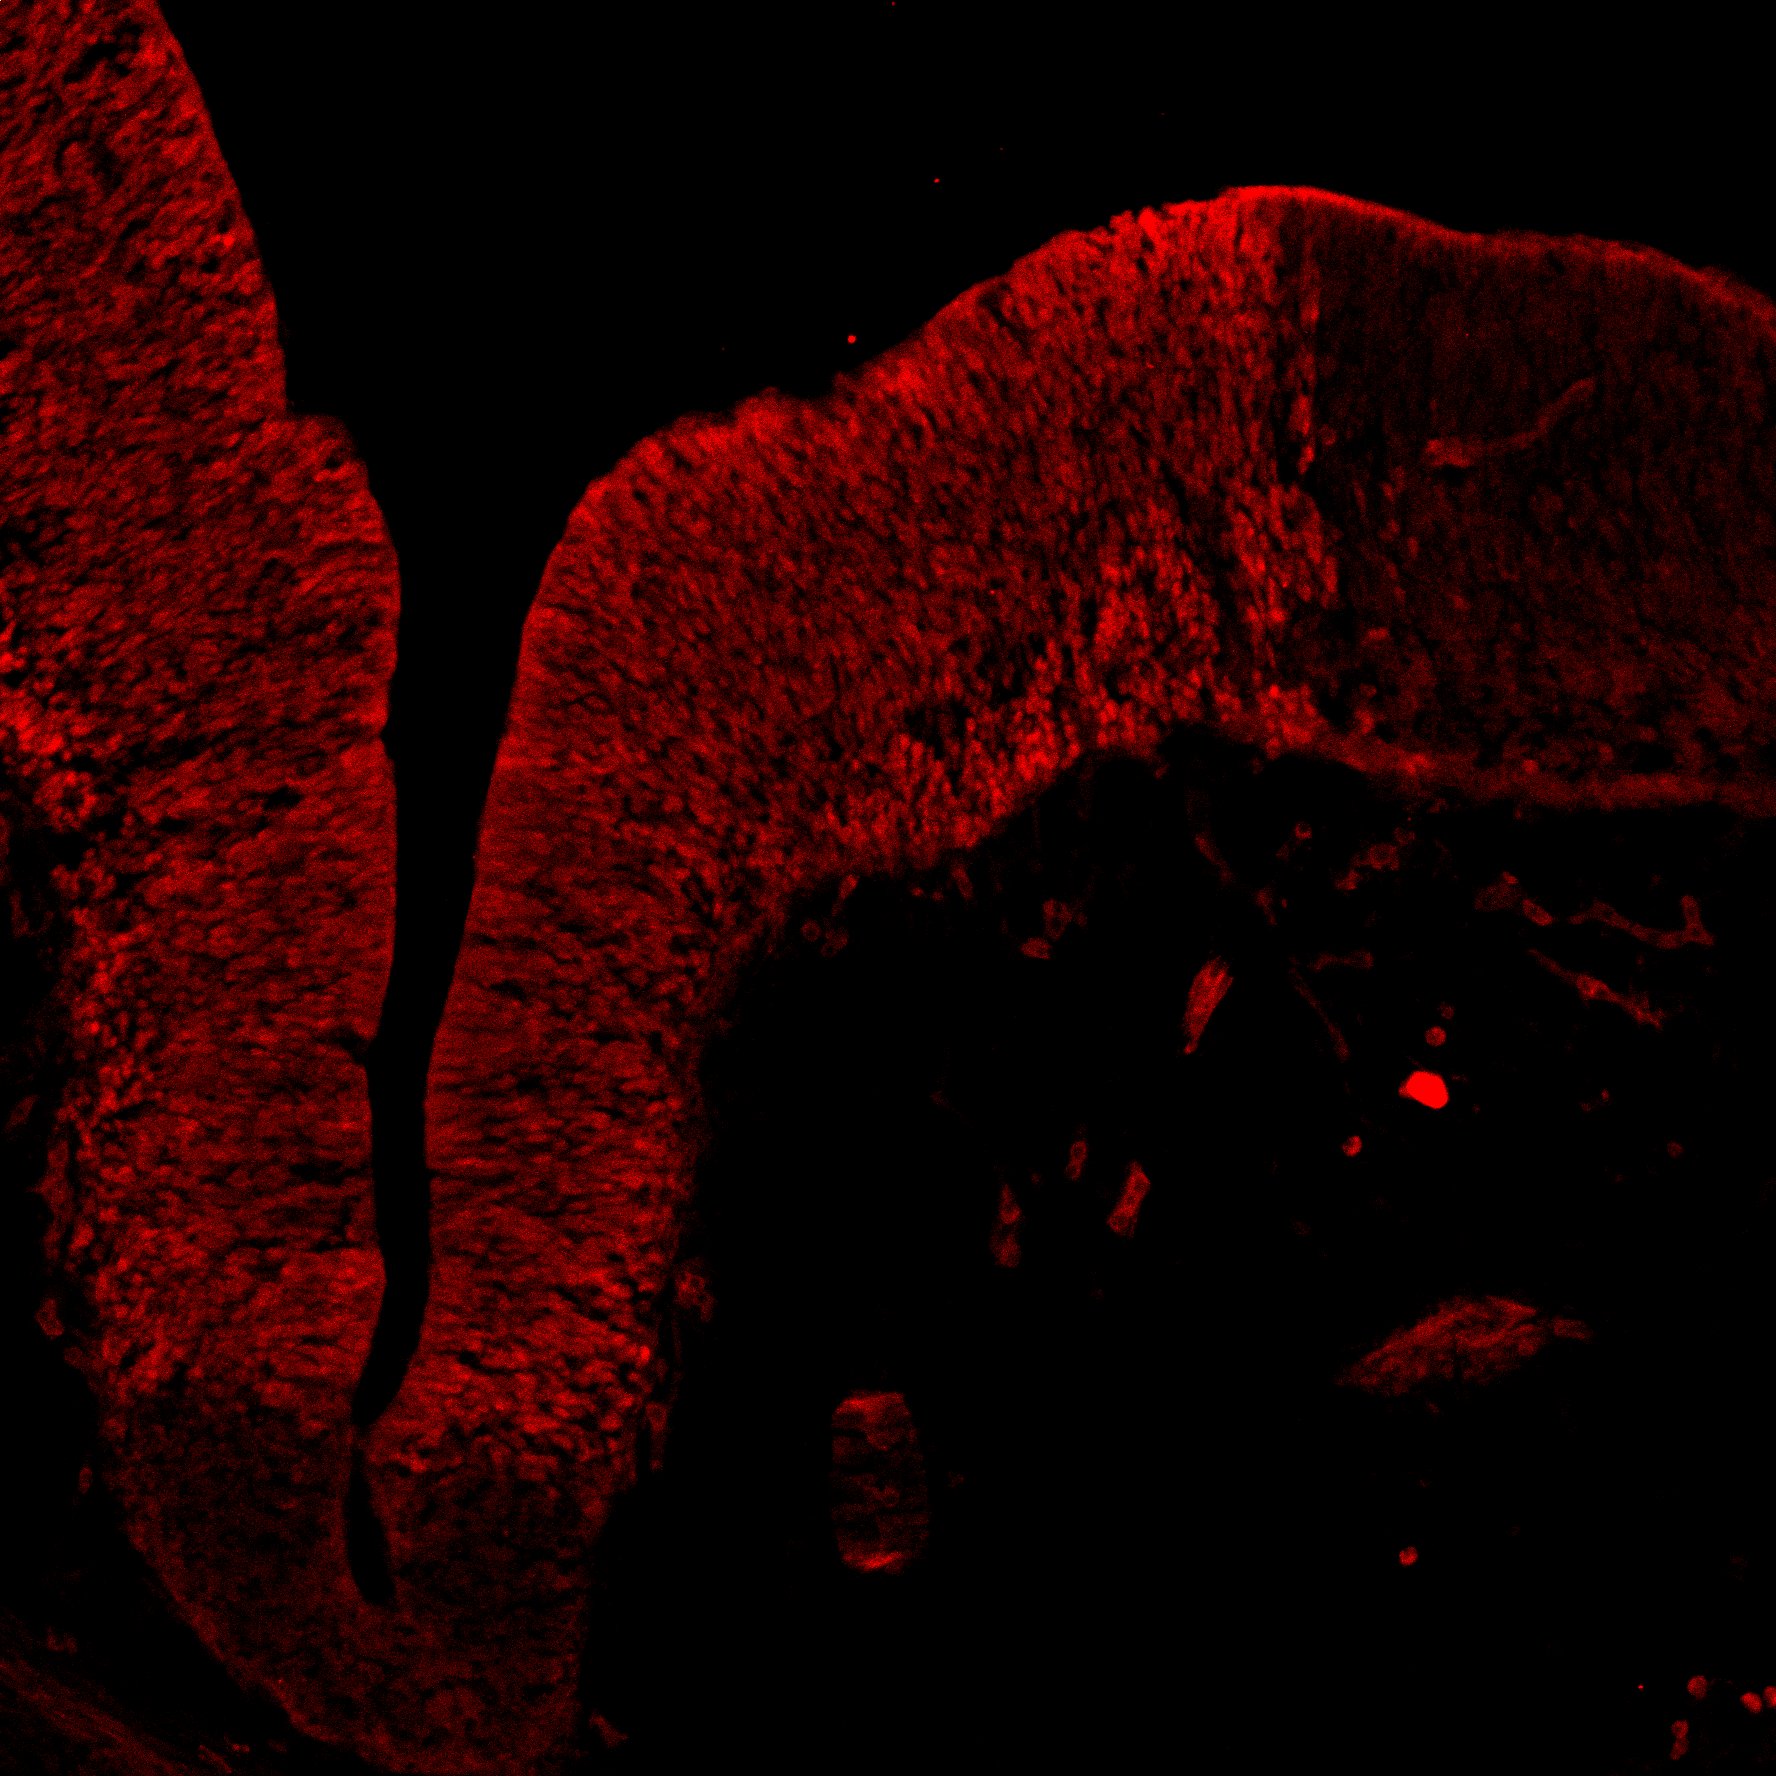

DAPI

11PCW human midbrain

TH

Merged